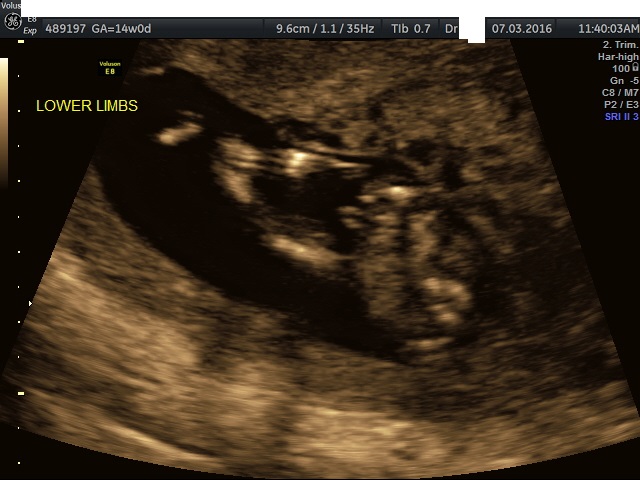

Lower Limbs Shot at 14 weeks- any clues?

I am 18+6 with baby number three and we have our morph scan next Thursday where hopefully we will hear bub is doing beautifully, and find out who will be joining our family. I have two gorgeous little ones, a 5 year old son and a daughter who was stillborn at 38+2 21 months ago. I am fairly certain this little one on board is another little man, but everyone around me (and perhaps me too a little, as awful as it sounds) is really hoping for another little girl, as this is likely to be our last baby. This shot was taken at 14 weeks and is the only one I have that may offer a clue, the only profile pic I'm pretty sure is baby's back.